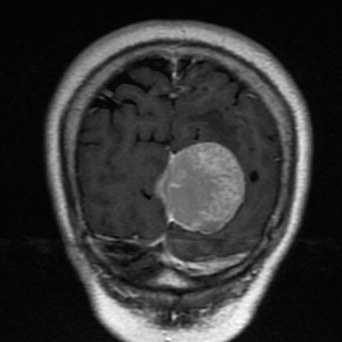

多学科协力成功切除镰旁脑膜瘤

近日,弋矶山医院专家刘策刚主任、赵心同主任和我院神经外科主任汪明义、ICU主任胡文涛、呼吸内科主任赵兴良、麻醉科主任张德文、感染科主任袁聂平等专家齐聚我院神经外科医师办公室,就一位左枕部镰旁占位(术后病理为:脑膜瘤

)

病人的病情展开多学科会诊及病历讨论。

该病人在我院通过颅脑磁共振增强检查出左侧大脑镰旁占位性病变,来我院要求手术治疗,在完善相关术前检查时,患者的胸部CT结果却给我们带来诸多疑惑。